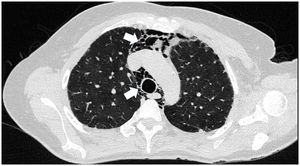

A 45-year-old man with a 2-year history of DM with positive anti-MDA5 antibodies and the classic muscular and cutaneous manifestations of this clinical phenotype (Fig. 3), in addition to ILD of the usual interstitial pneumonia type, which had been diagnosed 2 months earlier and for which he had been treated with a single dose of cyclophosphamide 750 mg IV. He consulted spontaneously due to sudden dyspnoea, and therefore underwent an angio-CT scan (Fig. 4) which showed, in addition to the underlying pulmonary fibrosis, concomitant pneumomediastinum and pneumothorax. Bronchoscopy and microbiological studies were performed, which were negative, and therefore we decided to continue with the next dose of cyclophosphamide, cyclosporine 3 mg/kg/day and start plasma exchanges. However, in the following days, after starting the therapies, the patient showed further respiratory deterioration and unfortunately died due to progression and exacerbation of ILD, in addition to a considerable increase in pneumomediastinum and pneumothorax despite having undergone thoracostomies by thoracic surgeons. The whole picture was considered to constitute a diagnosis of rapidly progressive ILD, and the patient eventually died.